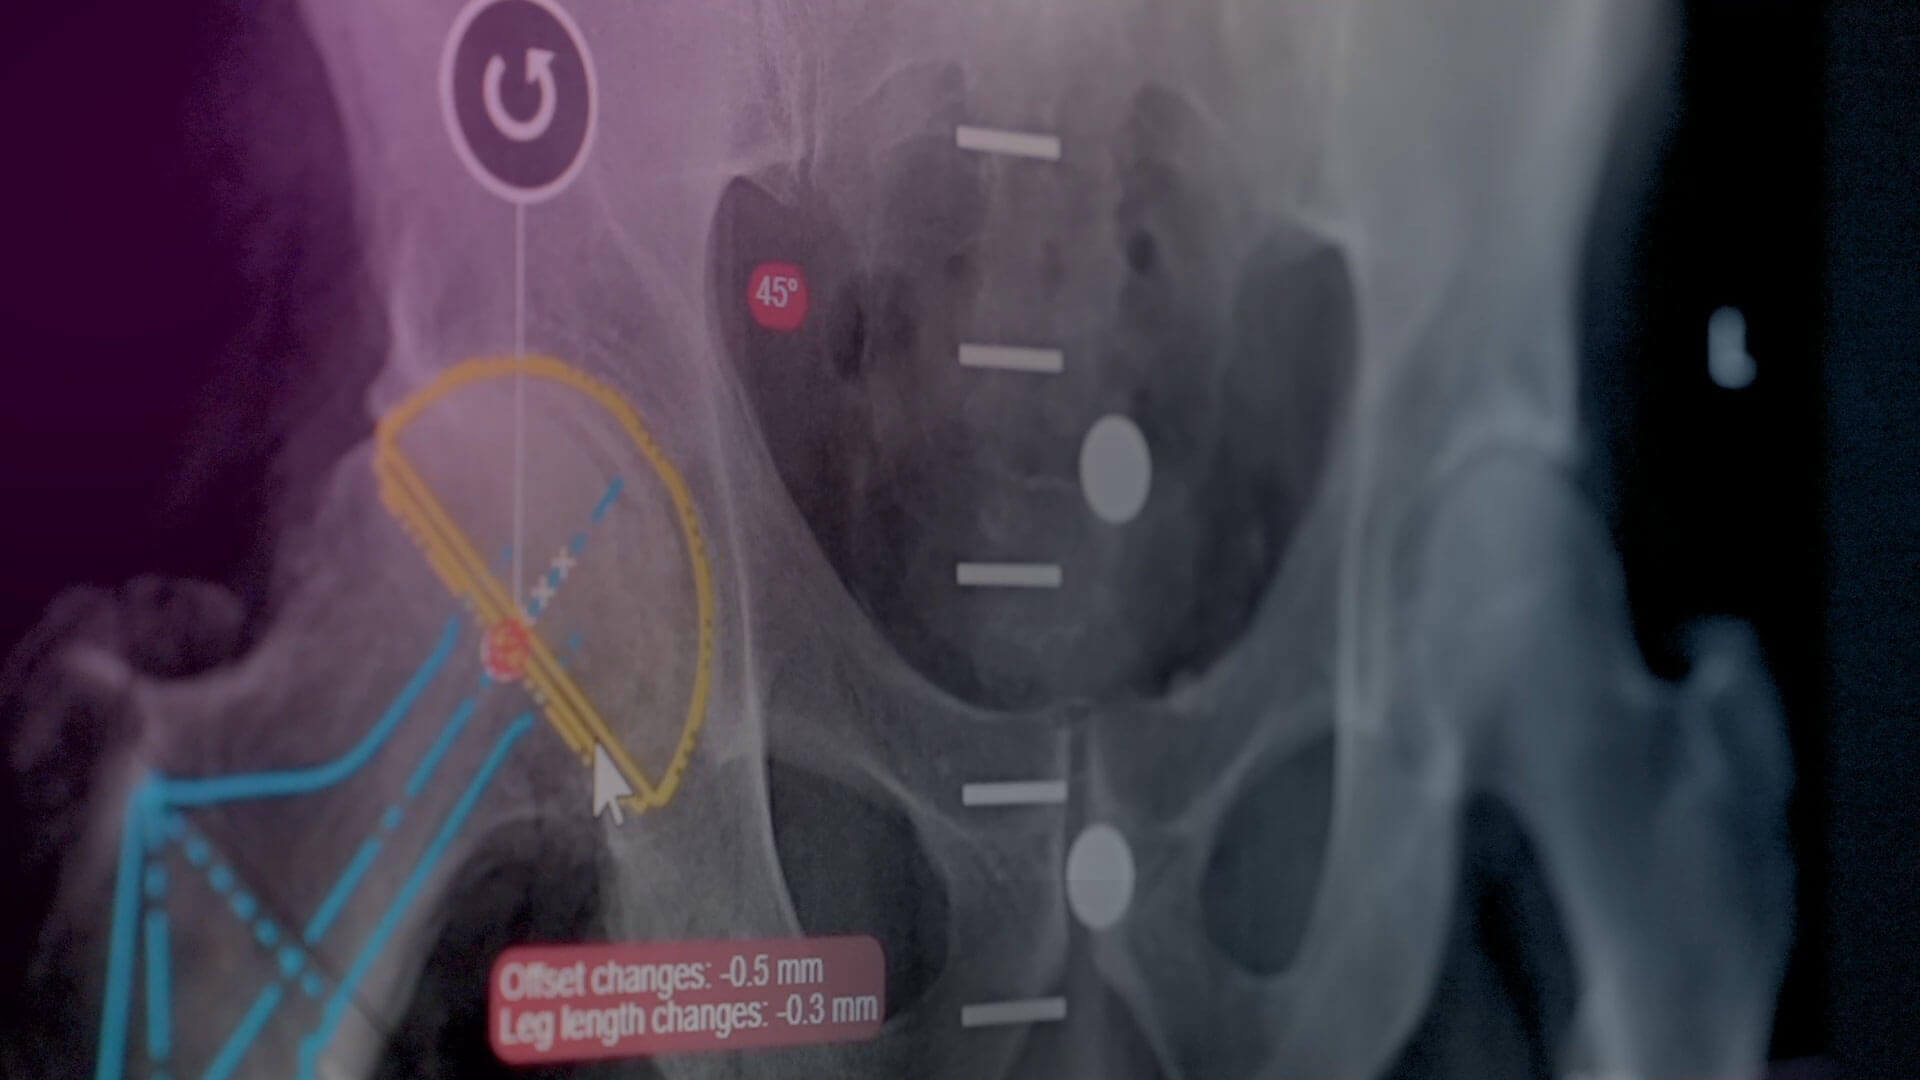

- Ortopédia

- TraumaCad®

- Sportsebészet

- Traumatológia

- Műszerek

- Műtőfelszerelések